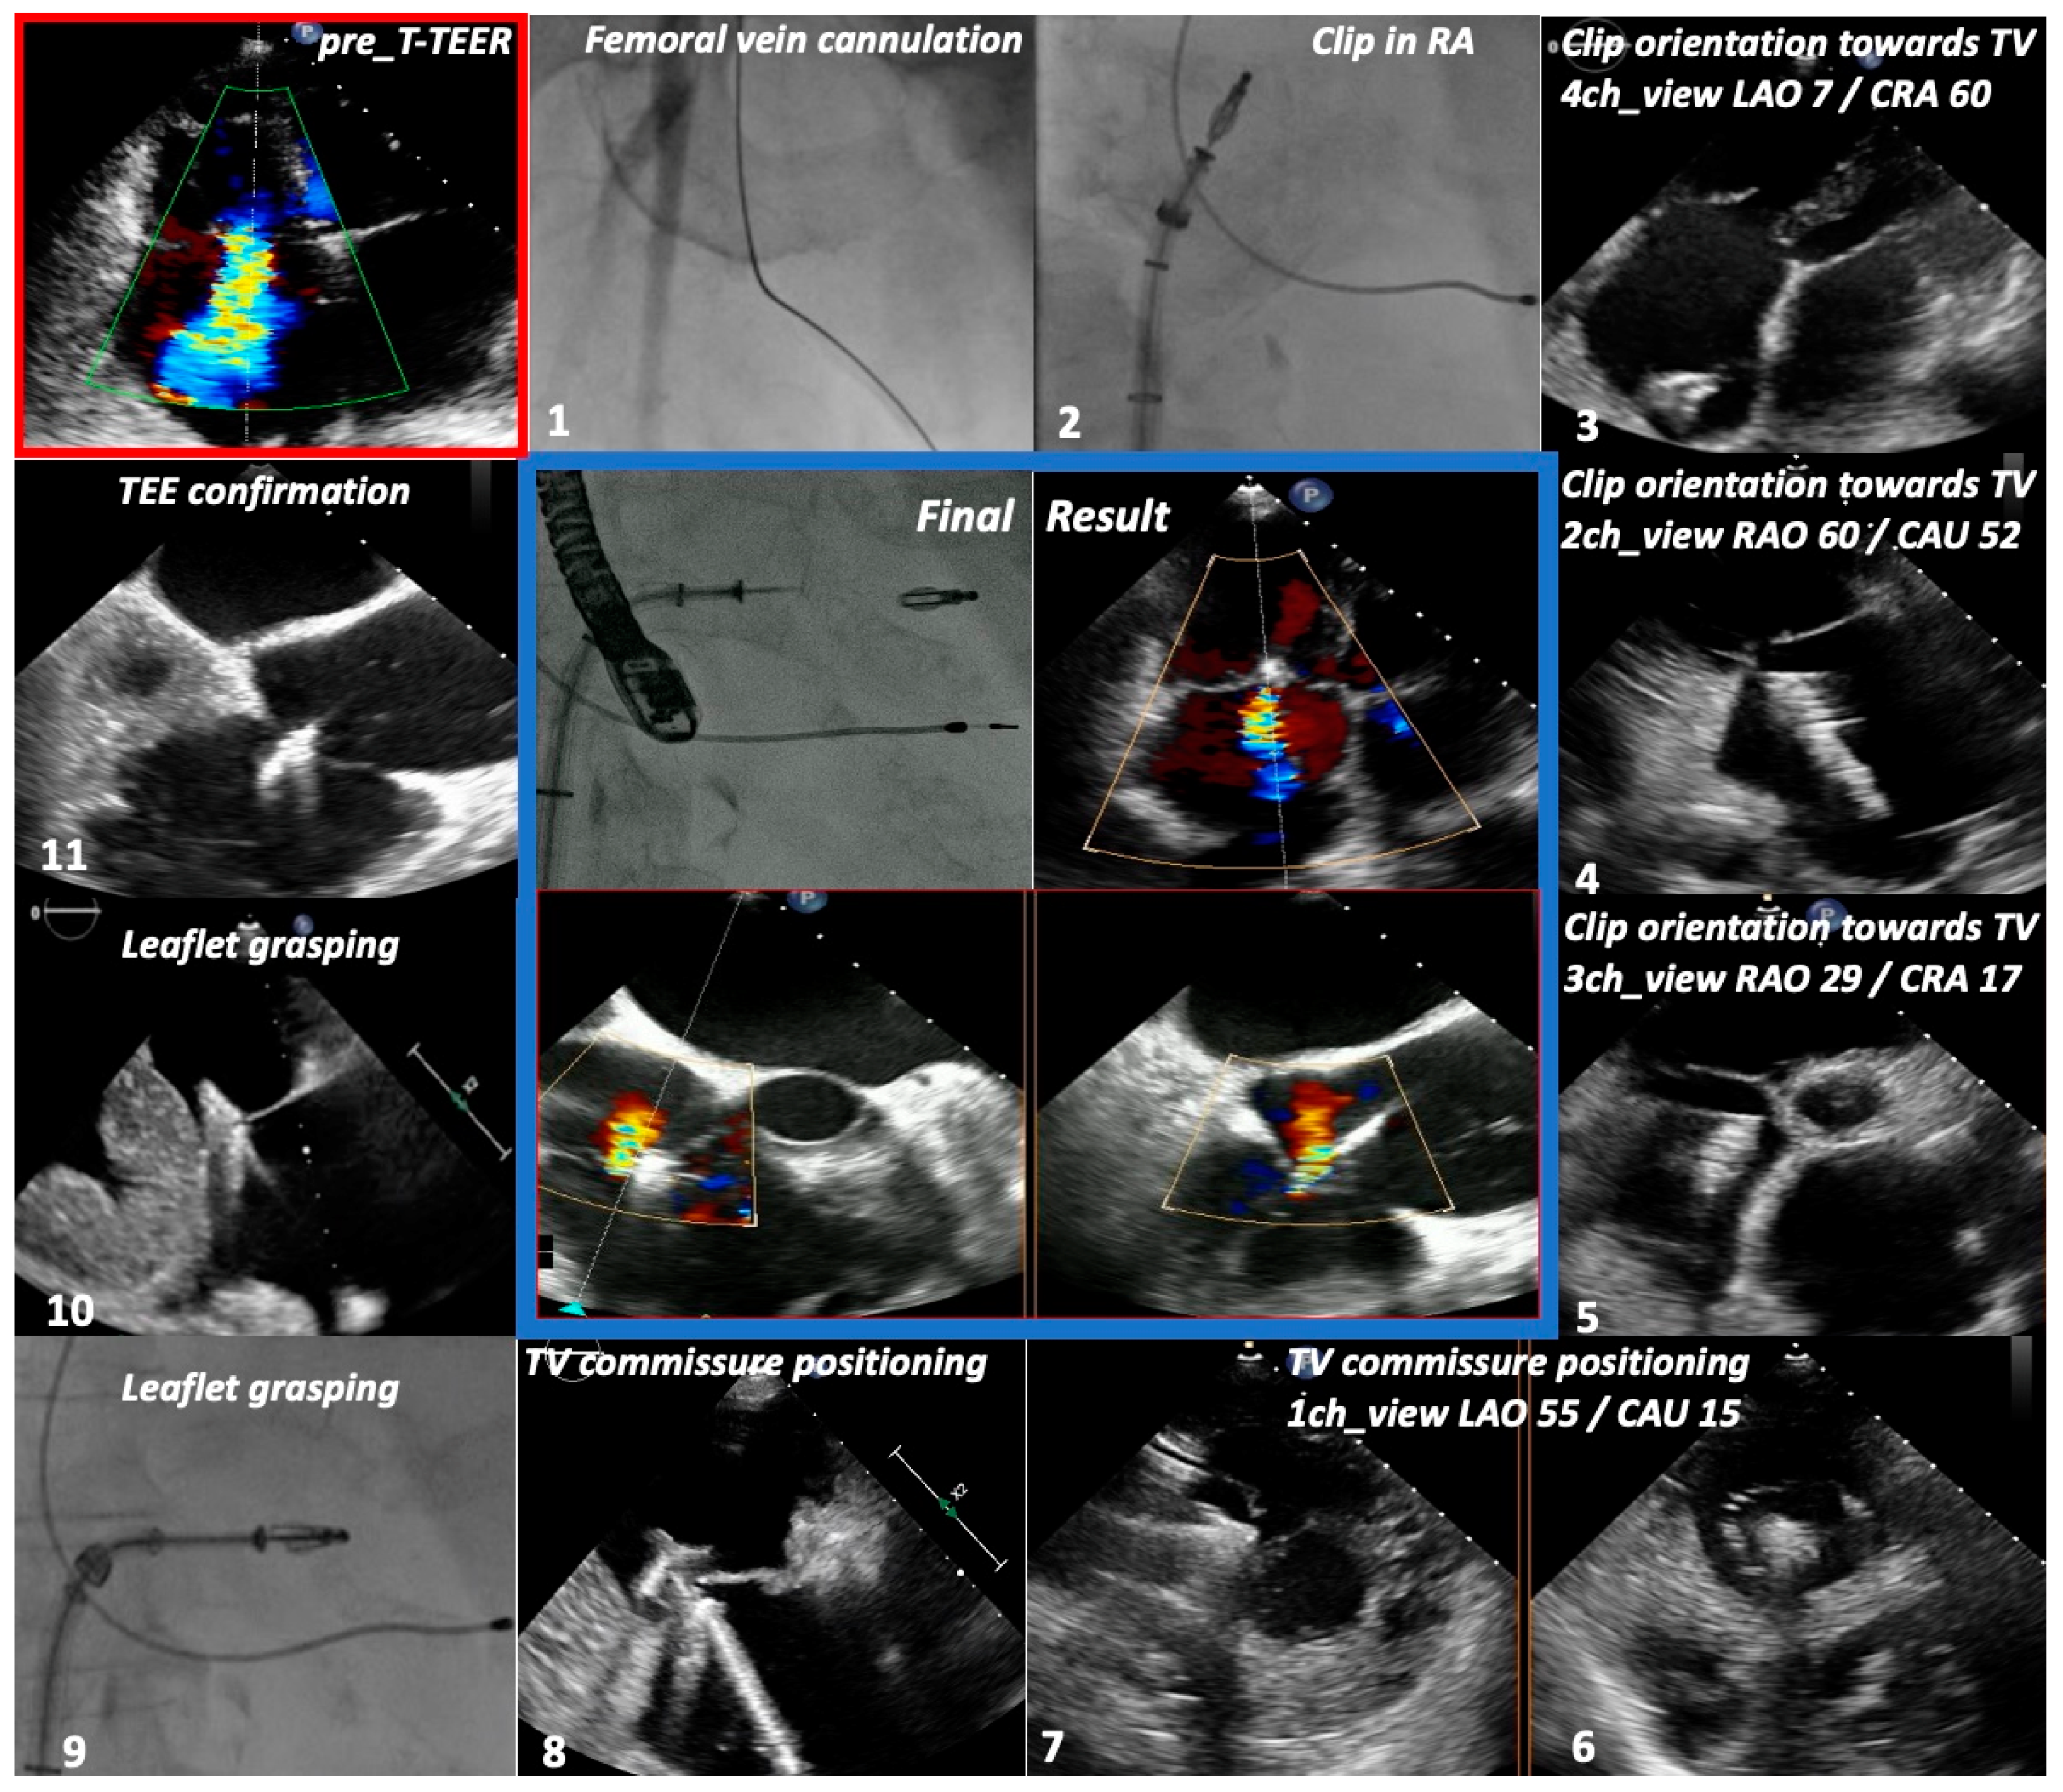

| TTE View | Focus | ||

|---|---|---|---|

| Functional Parameters | Right Heart Morphology | TV Anatomy | |

| PLA standard | LVOT diameter (Qs/CO calculation) | RV function and size (eyeballing) | -- |

| PLA RV inflow RH two-chamber view | TR severity (eyeballing) TR Jet VC and PISA (optional) | RV function and size (eyeballing) | AL visualization SL vs. PL distinction |

| PSA standard RH three-chamber view | TR severity (eyeballing) RVOT VTI RVOT diameter | RV size PA size | Leaflet distinction, if possible |

| PSA-modified alternative RH one-chamber view | TR severity (eyeballing) | TV annulus size Coaptation gap | Simultaneous visualization of all leaflets |

| A4C RH four-chamber view | TR Jet area, VC and PISA TR VTI, RVSP TAPSE RV free wall TDI RV FAC RA volume RV diameters LVOT VTI (A5C/A3C) | RV function and size RA size TV annulus size Tenting height | SL visualization AL vs. PL distinction |

| A2C right alternative RH two-chamber view | TR Jet area, VC and PISA | RA size TV annulus size | AL visualization |

| Subcostal long axis | Hepatic systolic vein flow reversal Inferior vena cava size | RV function and size (eyeballing) | PL visualization AL vs. SL distinction |

| Subcostal short axis RH one-chamber view | TR severity (eyeballing) | Coaptation gap | Simultaneous visualization of all leaflets |